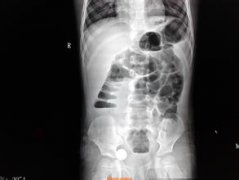

腸梗阻 是指任何原因引起的腸道通過障礙,而導致腸道和全身的病理變化。腸梗阻是小兒時期比較常見的急腹癥。 腸梗阻分類 腸梗阻大致可分為機械性(器質(zhì)性)和動力性(功能性)兩大類。 機械...

腸梗阻 是指任何原因引起的腸道通過障礙,而導致腸道和全身的...